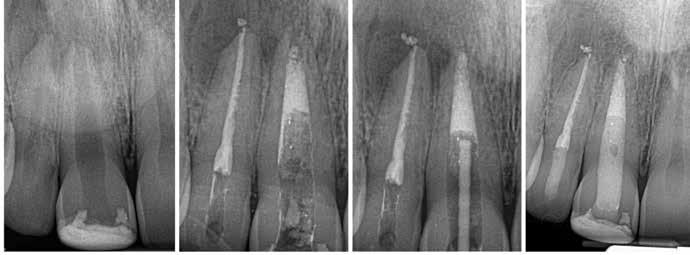

#13, #14 for ridge preservation. At a later date, three implant-supported crowns in close proximity were placed in these sites. Notably, the crowns were non-splinted. (Fig. 1).

In July 2021, the patient presented with mobile implants #12, #13 and #14 to his dental practitioner (Fig. 2). The implants were removed without bone grafting.

Fig. 1: May 2021. Panoramic radiograph shortly after placement of upper left #12, #13, #14.